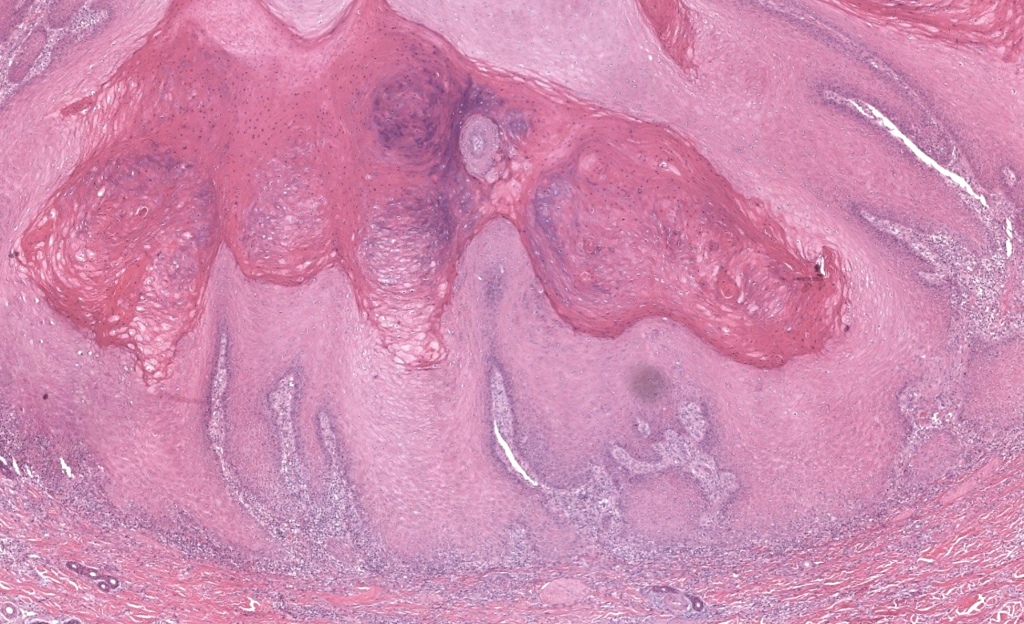

- Tumor epitelial escamoso cutáneo, bien diferenciado, de crecimiento rápido (semanas) y curso habitualmente autolimitado, con morfología en “cráter” relleno de queratina, pero con potencial de invasión local y, raramente, metástasis. Hoy se considera en la práctica clínica un CEC bien diferenciado de bajo grado (“CEC tipo queratoacantoma”, “carcinoma epidermoide queratoacantoma-like”). Kwiek 2016, Schwartz 2004

- Arquitectura crateriforme simétrica con base de empuje.

- Atipia leve-moderada, índice Ki-67 bajo-moderado, p53 no difuso.

- Ausencia de lengüetas infiltrativas profundas, invasión perineural y/o atipia marcada → QA clásico.